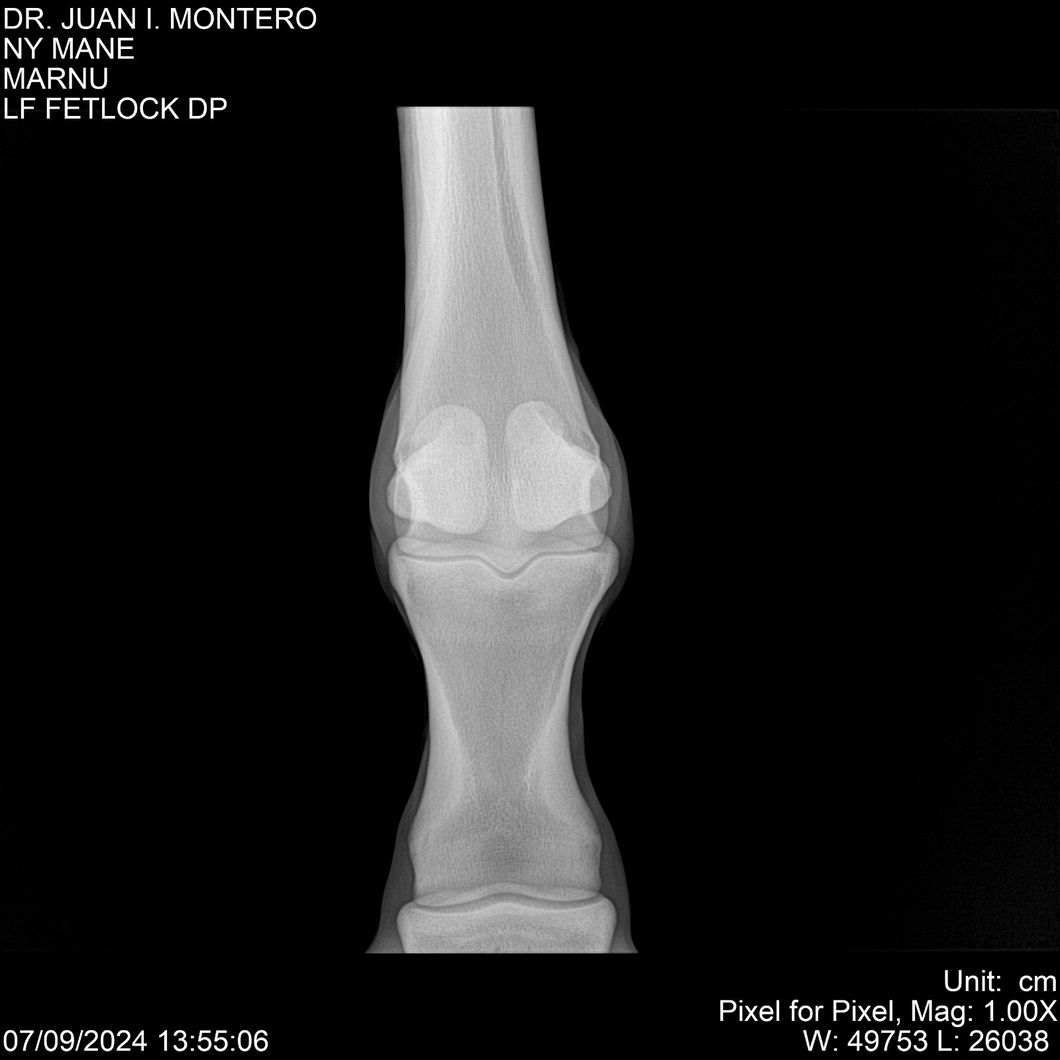

LOTE 20, NY MANE Lote Anterior Volver al remate Lote Siguiente Ficha Contacto Montevideo - Ficha del Lote Identificador: #282520 Categoría: Yeguarizos 76 Visualizaciones ClicData Contacto Empresa: Abelenda N. R., Walter Hugo Nombre*: Teléfono* : E-mail* : Mensaje Enviar Registrese gratis Este contenido Exclusivo está disponible sólo para usuarios registrados Ingresar